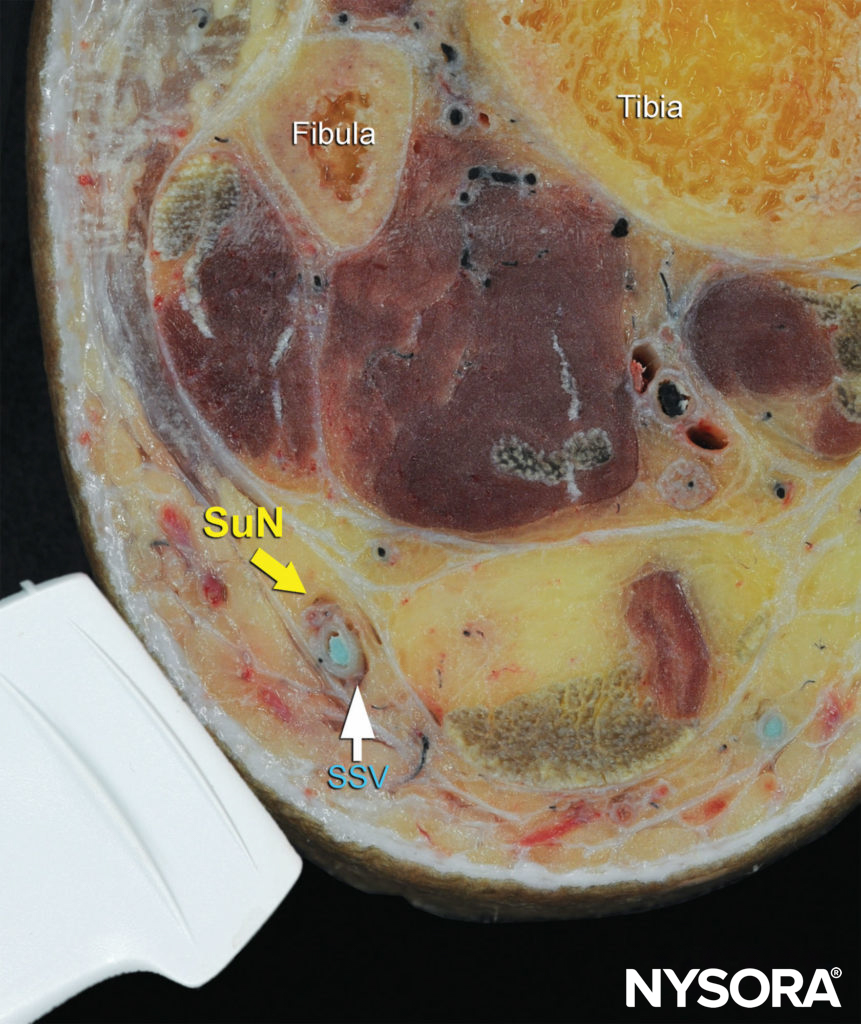

FIGURE 12. Cross-sectional anatomy of the sural nerve at the level of the ankle. Shown is the sural nerve (SuN) in the immediate vicinity of the small saphenous vein (SSV). (Reproduced with permission from Hadzic A: Hadzic’s Peripheral Nerve Blocks and Anatomy for Ultrasound-Guided Regional Anesthesia, 2nd ed. New York: McGraw-Hill, 2011.)

The sural nerve, can be traced back along the posterior aspect of the leg, running in the midline superficial to the Achilles tendon and gastrocnemius muscles (Figures 11, 12, and 13). A calf tourniquet can be used to increase the size of the vein and facilitate its imaging; the nerve is often found in the immediate vicinity of the vein.

The sural nerve innervates the lateral margin of the foot and ankle. Proximal to the lateral malleolus, the sural nerve can be visualized as a small hyperechoic structure that is intimately associated with the small saphenous vein superficial to the deep fascia.